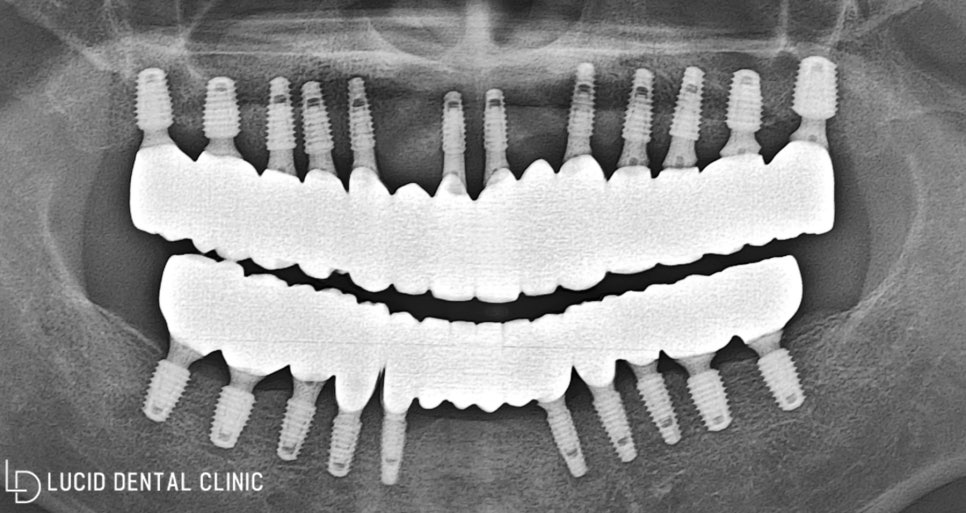

사진과 같이 위, 아래

총 12개의 픽스처를 식립하고

구강 환경이 모두 회복될 때까지

임시 틀니를 사용하도록 했습니다.

일부러 치아 하나하나 모두 식립하지 않고

필요한 부분만 픽스처를 심어두었습니다.

브릿지 형태의 보철로 제작하여

비용 부담을 줄여드릴 생각이죠.

사진과 같이 최종 보철을 체결하고

마무리 작업까지 모두 마쳤는데요

전체 임플란트 수술 이 끝나고

정기 검진을 받으러 오셨을 때

한 번 더 촬영 및 진단하며 확인하니

안정된 모습을 보이고 있었습니다 :)